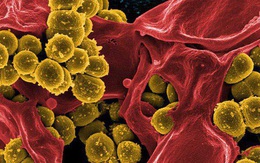

Cảnh báo loại vi khuẩn nguy hiểm kháng nhiều loại kháng sinh: Nếu nhiễm rất khó điều trị, tiên lượng tử vong cao

29/11/2020 20:51

Tụ cầu vàng là vi khuẩn trong nước, đất, thậm chí sống ký sinh trên da và có thể xâm nhập vào cơ thể qua những vết thương nhỏ. Nếu không cấp cứu kịp thời sẽ tử vong.